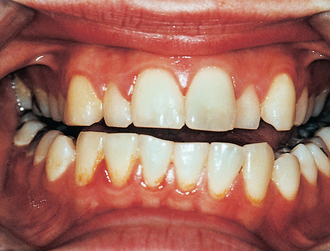

Examination of jaw function should include measurement in millimetres of maximal comfortable mouth opening from the tips of the central incisors on one side; this should be recorded clearly in the medical records. Abnormalities of jaw function should be sought and recorded: these include deviation on opening, abnormal joint sounds and disrupted occlusion (Fig. 13.5). Temporomandibular joint dislocation is rarely a result of injury but traumatic effusions can give rise to temporary mild posterior open bite. Crucially, anterior open bite can be a feature of Le Fort pattern fractures in which the middle third of the facial skeleton moves backwards and downwards on the cranial base or of bilateral fractures of the mandibular condyles in which the pterygomasseteric sling shortens the ascending rami.

image

Fig. 13.5 Anterior open bite associated with fracture of the mandible.